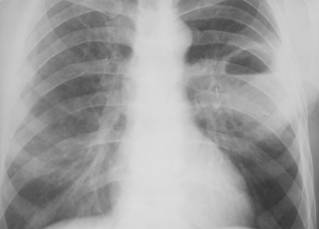

Tuberculoza secundara – apare la un interval de timp variabil dupa prima infectie, dar propagarea este predominant bronhogena. Se manifesta sub forma infiltratelor tuberculoase: opacitati rotund-ovalare, omogene, de intensitate redusa, situate subclavicular, interesand in special segmentul posterior al lobilor superiori:

Fig. 19 – Infiltrat Assman excavat

Infiltratul rotund subclavicular Assman – se prezinta sub forma unei opacitati rotunde, de 1-3 cm diametru, de intensitate mica, contur sters, structura omogena si dinamica foarte vie (se poate resorbi sau excava in 2-3 saptamani);